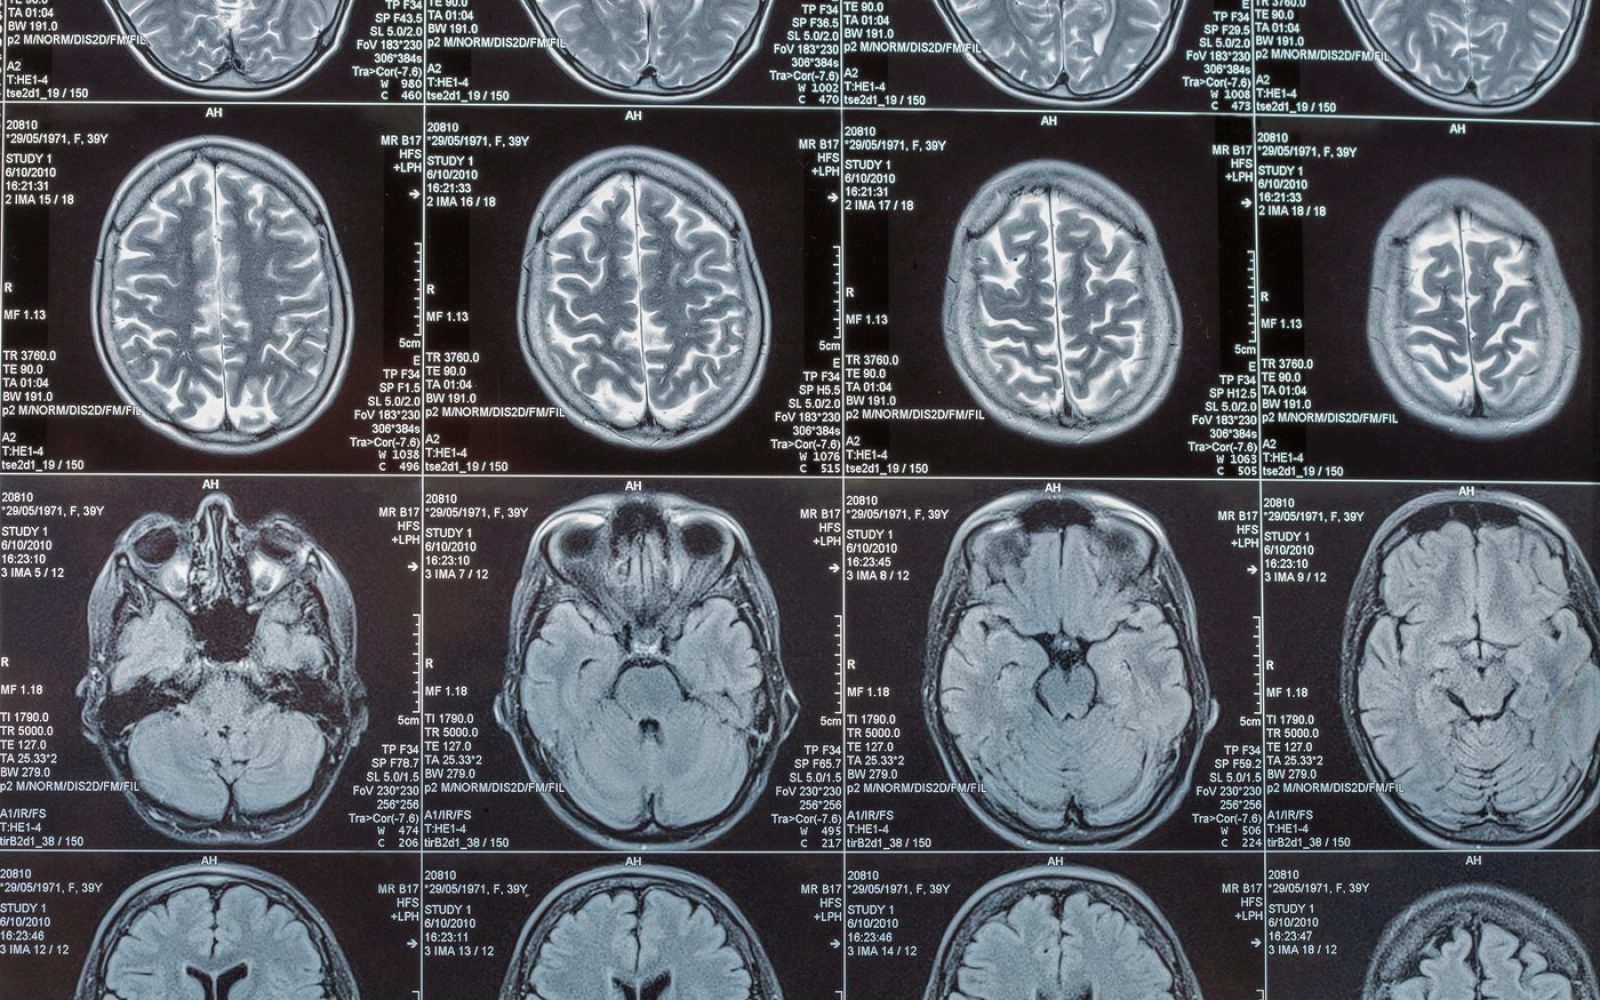

Testi so razkrili, da ima Amy astrocitom četrte stopnje, agresiven možganski tumor, ki je že dosegel velikost žogice za golf.

Po operaciji, radioterapiji in kemoterapiji je Amy verjela, da je bolezen premagala, dokler nedavni letni pregled ni pokazal, da se je tumor po desetih letih vrnil. Srce parajoča novica je prišla kmalu zatem, ko je Amy zaznala zamegljen vid in nerazločen govor. Zdravniki pravijo, da ima pred seboj največ devet mesecev življenja.

“Tumorji centralnega živčnega sistema (CŽS) so redki. V Sloveniji je v letu 2021 za različnimi tumorji CŽS zbolelo 179 ljudi. So raznolika skupina bolezni, ki se razlikujejo glede na svoje histopatološke značilnosti. Najpogostejše jih delimo na astrocitne tumorje, oligodendrocitne tumorje, ependimome, meningeome in primitivne nevroendokrine tumorje. Astrocitome delimo na nizko in visoko maligne. Nizko maligni astrocitomi se pogosteje pojavljajo v mlajših starostnih skupinah. Med visoko maligne astrocitome spadata anaplastični astrocitom in glioblastom. Pogosteje se pojavljata v starejših starostnih skupinah in pogosteje zbolijo moški. Preživetje bolnikov je boljše v mlajših starostnih skupinah,” pišejo na spletni strani Onkološkega inštituta Ljubljana.